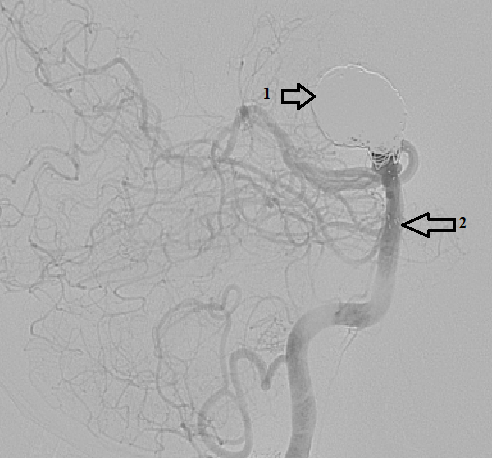

При ангиографии из левой ПА визуализируется крупная мешотчатая частично тромбированная аневризма бифуркации основной артерии размером 18*15*16 мм с широкой шейкой 11 мм. В состав аневризмы инкорпорированы истоки обеих задних мозговых и верхних мозжечковых артерий.

С использованием триаксиальной системы в V3-сегмент левой ПА заведен направляющий катетер Fargomax 6F. Затем в правую ЗМА (Р-2 сегмент) заведен микрокатетер SL10 при помощи микропроводника Traxcess14. После этого введен, позиционирован и имплантирован из ЗМА в ОА стент NeuroformAtlas 4,0*21 мм. При контрольной ангиографии стент и церебральные ветви левой ЗМА проходимы, метки стента разошлись полностью.

Следующим этапом через ячейку иплантированного стента в левую ЗМА (P-3 сегмент) заведен микропроводник Traxcess14, по которому заведен микрокатетер SL10 в Р-2 сегмент ЗМА. При помощи микропроводника Traxcess14 в купол аневризмы для дальнейшей эмболизации аневризмы микроспиралями введен микрокатетер SL1018. Затем через предустановленный в левую ЗМА SL10 введен, позиционирован и имплантирован стент NeuroformAtlas 4,5*21 мм. При контрольной ангиографии стент и церебральные ветви правой ЗМА проходимы, метки стента разошлись полностью. Следующим этапом в купол аневризмы последовательно под этапным ангиографическим контролем введено и имплантировано 15 микроспиралей Target. При контрольной ангиографии отмечается пришеечное контрастирование аневризмы, стенты и церебральные ветви ВББ проходимы, бессосудистых зон нет